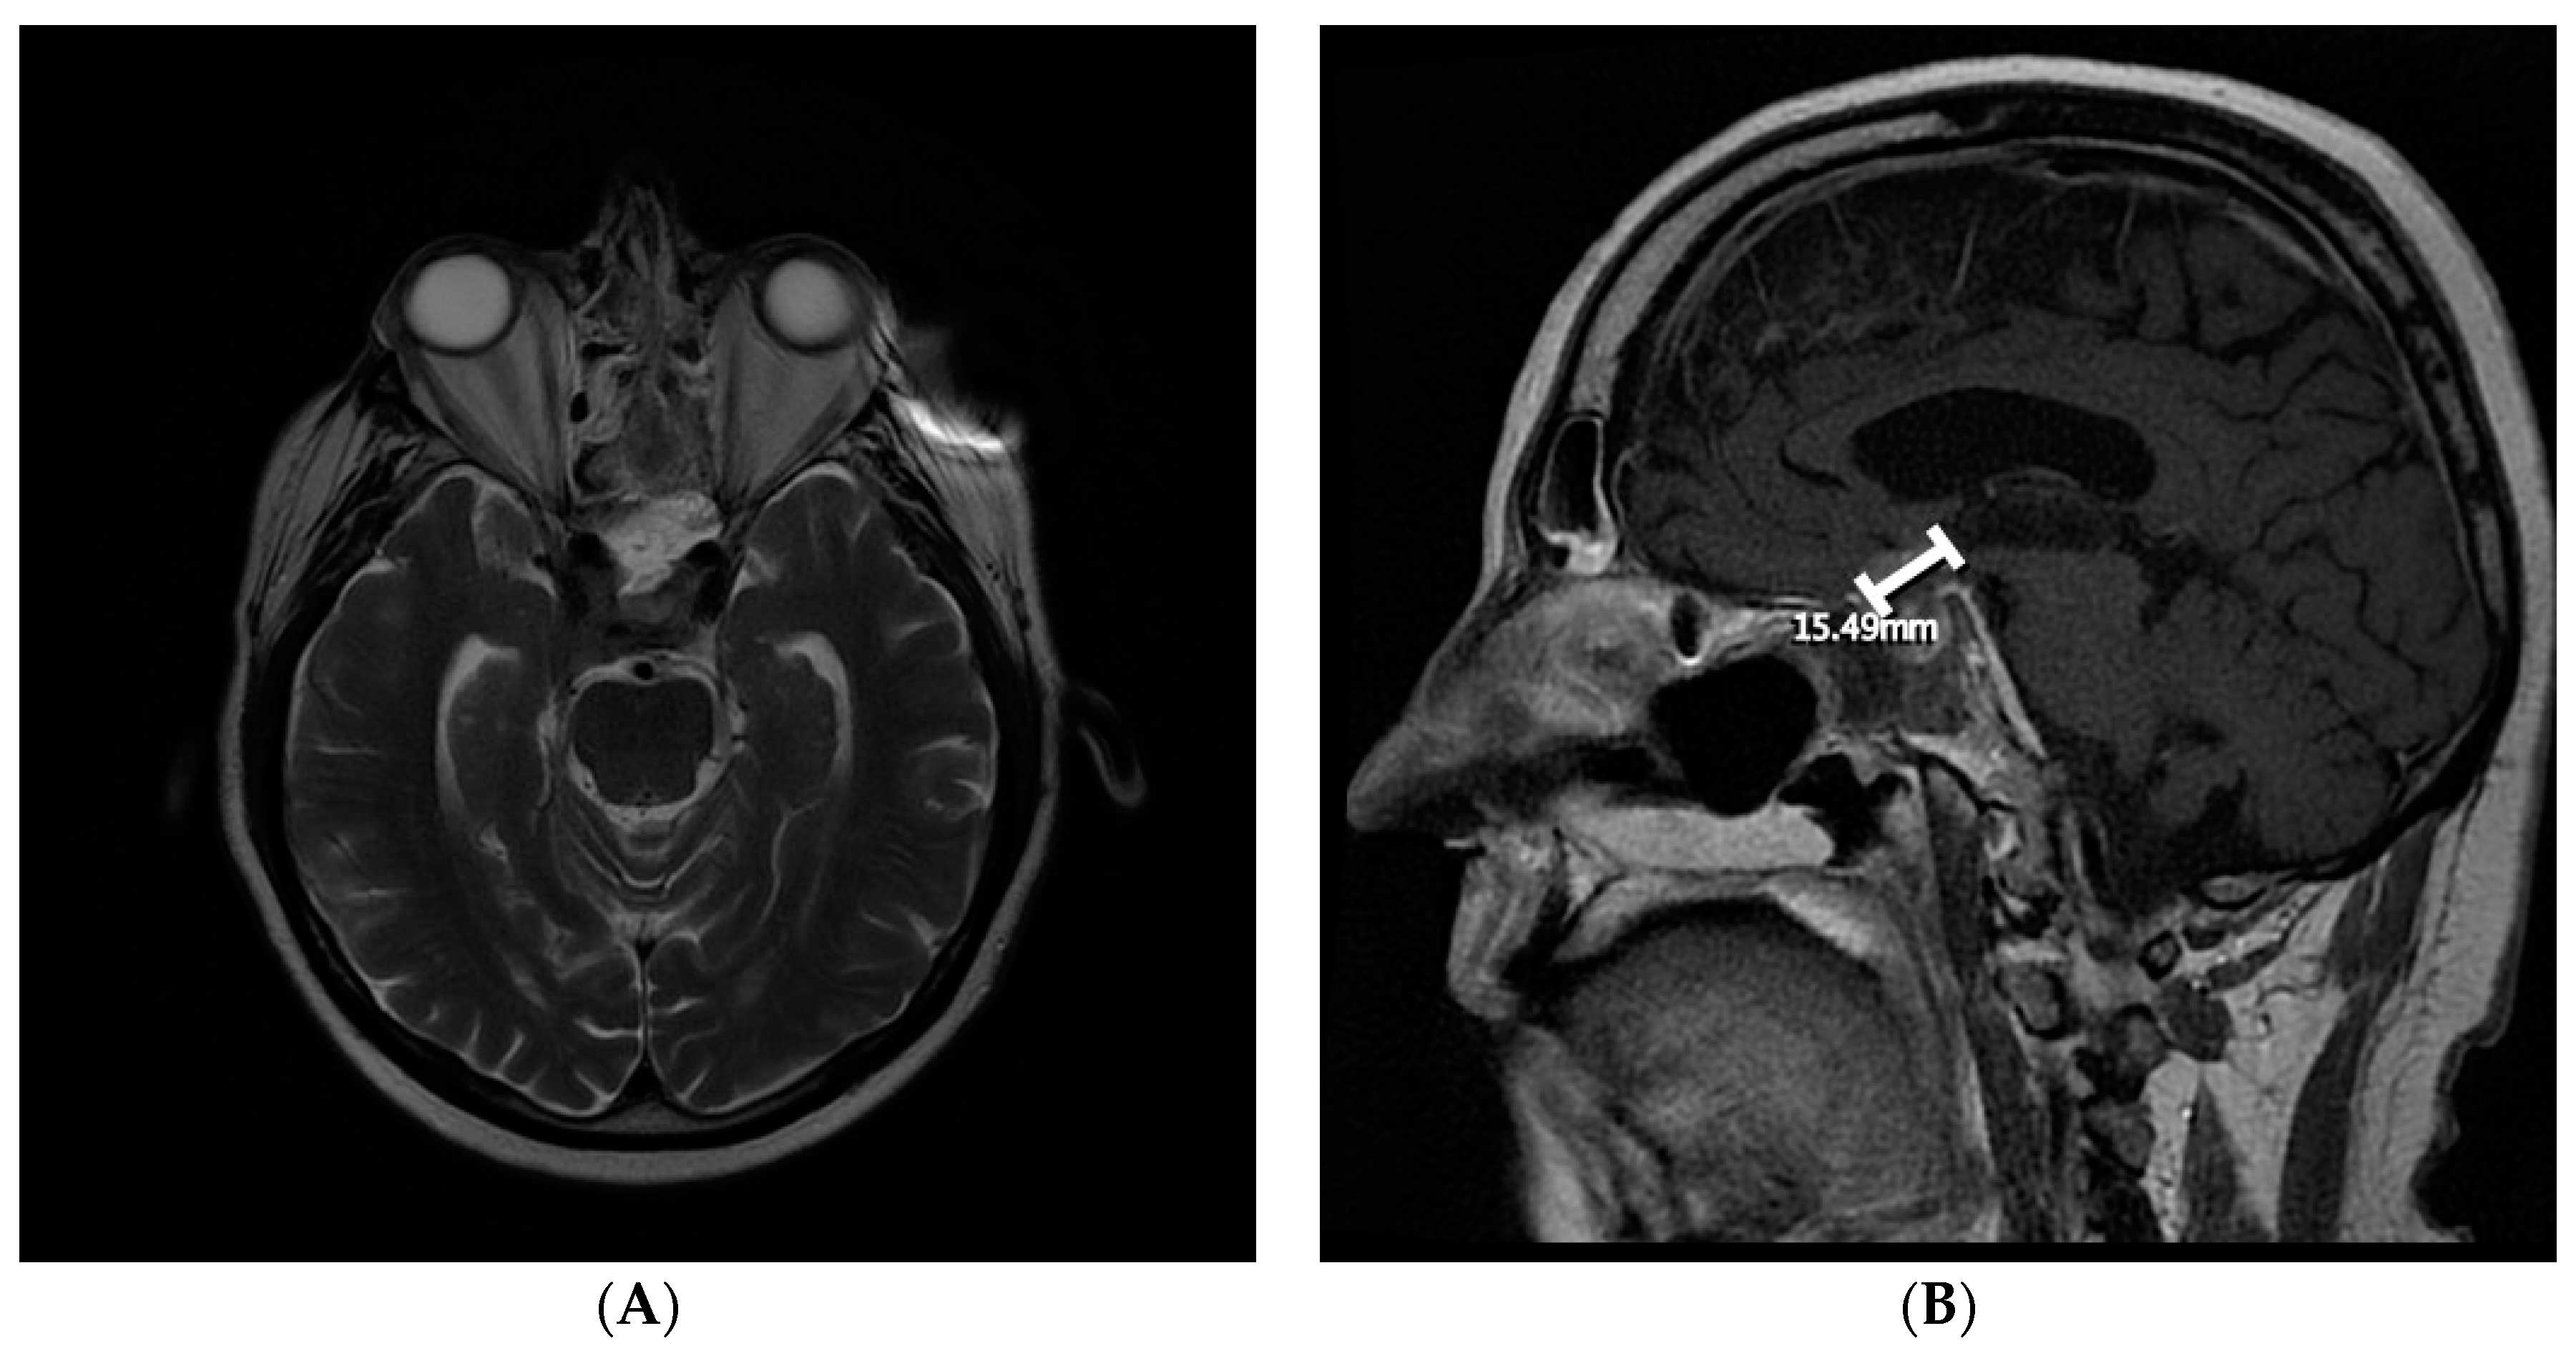

By August 2018, the patient had developed bitemporal hemianopsia and decreased visual acuity, which progressed to complete visual loss. Transnasal transsphenoidal endoscopic resection of the mass was performed in September 2018, and navigation MRI performed during surgery revealed that the initial lesion had doubled in size, and that there was another right temporal lesion. Surgical excision was subtotal (Figure 3). Final pathology results indicated that the most likely diagnosis was metastatic adenocarcinoma, consistent with a prostatic primary tumor (sellar tumor). After surgery, more brain lesions were identified in the hypothalamus extending into the right basal ganglia and a dural base lesion.

Figure 3. Follow-up postsurgical magnetic resonance imaging of the brain (September 2018) revealing subtotal surgical excision of the sellar metastatic lesion. (A) Axial view; (B) sagittal view.